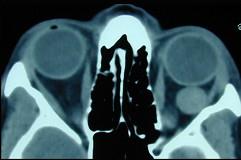

成人眶内最常见的良性肿瘤是 ( )A、脑膜瘤B、视神经鞘瘤C、甲状腺相关性眼病D、海绵状血管瘤(如图)E、炎性假瘤

选项 A、脑膜瘤 B、视神经鞘瘤 C、甲状腺相关性眼病 D、海绵状血管瘤(如图) E、炎性假瘤

答案 D